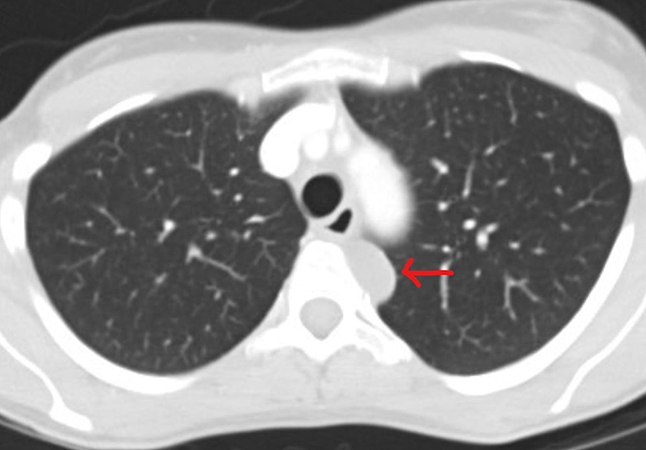

Clinical History: A 43-year-old woman was referred for a thoraco-abdomino-pelvic CT scan following mild unintentional weight loss in the context of a significant family history of colorectal cancer. There was no significant personal past medical history, and the patient was a non-smoker. Prior colonoscopy and gastroscopy were normal. The only finding on CT was 2 cm cystic lesion of the left posterior mediastinum. Follow up imaging 6 months later showed that the cyst had increased to 3 cm in size (Figure 1) and an excision was performed. Intraoperatively the lesion was extrapulmonary and adherent to the pleura of the posterior mediastinum, however the surgeon noted that complete surgical excision without rupture was achieved. Macroscopically the specimen consisted of two thin (~0.2 cm) fragments of uniform fibro-membranous tissue without excrescences or nodules, the largest of which was 2.5 cm in greatest diameter. The specimen was entirely submitted for histologic examination. Histologic sections showed relatively uniform bands of epithelial lined fibrous tissue with occasional luminal papillary-like extensions and tubular involutions (Figures 2, 3, 4). No cartilage, submucosal type glands, or thymic tissue were identified. Representative positive immunohistochemical stains are provided (Figures 5, 6).